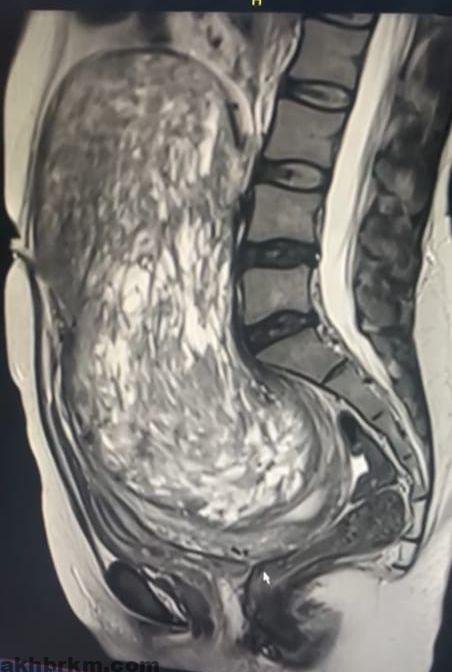

نجح فريق طبي في مدينة الملك عبدالله الطبية، عضو تجمع مكة المكرمة الصحي، في إجراء عملية جراحية دقيقة لاستئصال ورم بحجم جنين بحجم 30×15 سم من سيدة سعودية في العقد الثالث من العمر.

وأوضح تجمع مكة المكرمة الصحي: أن المريضة كانت تعاني من ضغوطات شديدة بسبب الورم الذي أثر على الشريان الأورطي البطني والوريد الأجوف السفلي، بالإضافة إلى الجهاز الهضمي مسببًا انسدادًا جزئيًا وإمساكًا مزمنًا. كما تسبب الورم بضغط على المثانة البولية والأعصاب، ما أدى إلى آلام وتنميل في الأطراف السفلية.

وأشار: إلى أن الفريق الطبي قام بالتحضيرات للعملية شملت إجراء فحوصات مخبرية وأشعة دقيقة، بالإضافة إلى معاينة شاملة من قبل قسم التخدير لضمان أعلى معايير السلامة الطبية. وبعد تخطيط دقيق، تم إجراء العملية عبر فتح البطن واستئصال الورم بالكامل مع الحفاظ على الرحم والمبيضين، حيث استغرقت العملية ثلاث ساعات تكللت بالنجاح ولله الحمد.